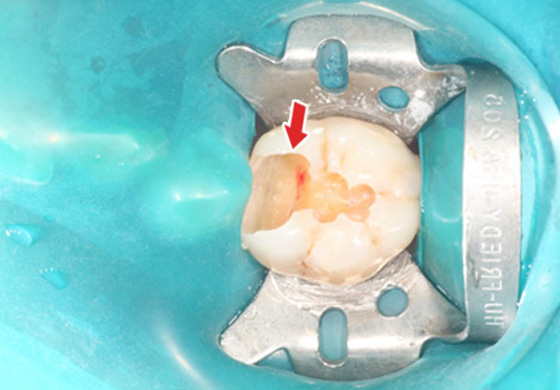

¡ã ÃæÄ¡Ä¡·á Áß¿¡ Ä¡¼ö°¡ ³ëÃâµÈ ¸ð½À